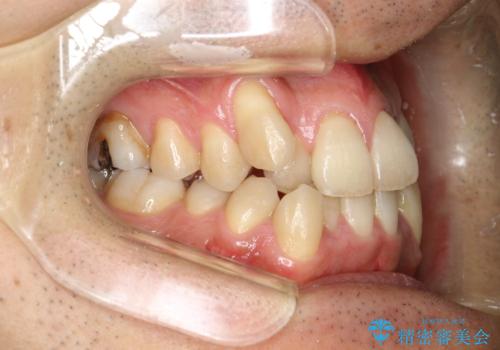

ガタガタの歯並び、八重歯をなおしたい、骨格性下顎前突 カモフラージュ矯正

- 前歯のガタガタと八重歯を治したいということで矯正を希望された患者様です。

骨格的に上顎骨が小さいために相対的に下顎骨が前に出ていたため、歯の傾きなど理想的な仕上がりが難しく、外科矯正ではなく歯列矯正の場合はカモフラージュ矯正になること説明の上、矯正治療を進めることになりました。

上顎は左右5番抜歯、下顎は左右4番抜歯しています。